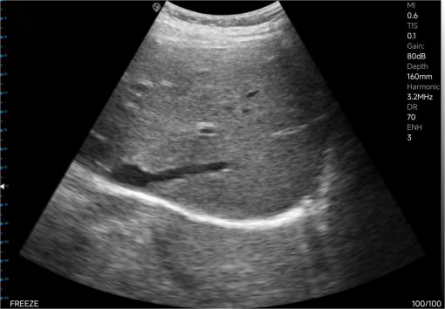

The left image shows the normal depth, and the right image shows the magnified view.